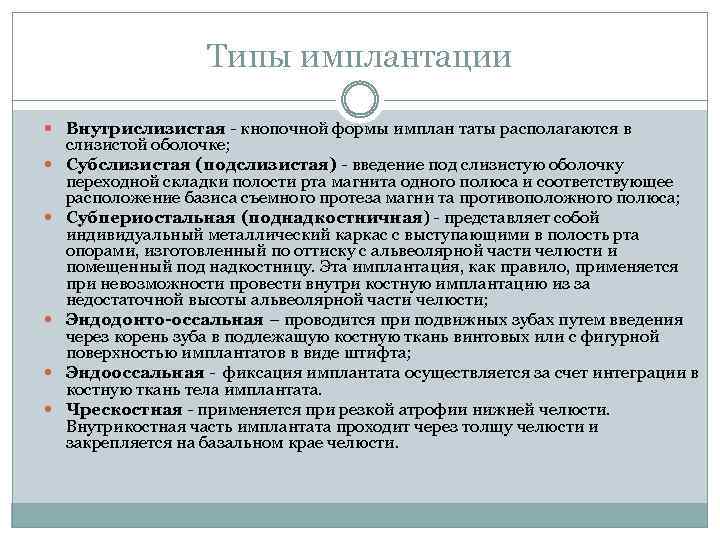

Типы имплантации Внутрислизистая кнопочной формы имплан таты располагаются в слизистой оболочке; Субслизистая (подслизистая) введение под слизистую оболочку переходной складки полости рта магнита одного полюса и соответствующее расположение базиса съемного протеза магни та противоположного полюса; Субпериостальная (поднадкостничная) представляет собой индивидуальный металлический каркас с выступающими в полость рта опорами, изготовленный по оттиску с альвеолярной части челюсти и помещенный под надкостницу. Эта имплантация, как правило, применяется при невозможности провести внутри костную имплантацию из за недостаточной высоты альвеолярной части челюсти; Эндодонто-оссальная – проводится при подвижных зубах путем введения через корень зуба в подлежащую костную ткань винтовых или с фигурной поверхностью имплантатов в виде штифта; Эндооссальная фиксация имплантата осуществляется за счет интеграции в костную ткань тела имплантата. Чрескостная применяется при резкой атрофии нижней челюсти. Внутрикостная часть имплантата проходит через толщу челюсти и закрепляется на базальном крае челюсти.